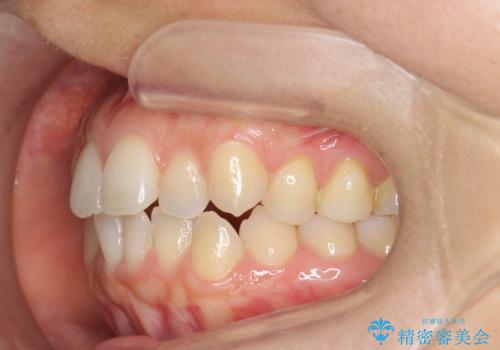

前歯のがたつきをしっかり治すマウスピース矯正

- 前歯のガタガタをきれいに並べたい、と希望され来院されました。

がたつきのないきれいな歯並びに仕上げることができ、満足いただくことができました。